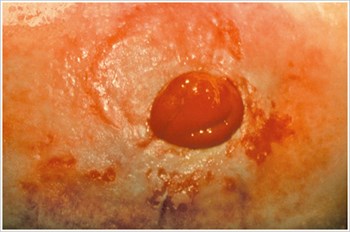

Úlcera por pressão

Descrição/Causas:

Úlcera na área peristomal, causada por pressão excessiva proveniente de uma cinta de aparelhos de estomia, roupas apertadas, hérnia peristomal ou hábitos relacionados ao trabalho.

Sintomas:

- Dor ou sangramento

- Úlcera com formato irregular

- Vazamento na bolsa

- Menor tempo de uso